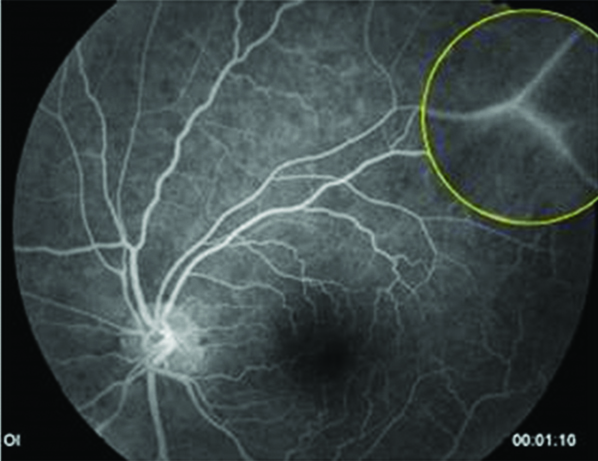

Fue derivada a oftalmología por presentar dificultad en la visión, descripta como ¨falta de visión periférica¨, alteración compatible con escotoma temporal superior en ambos ojos (AO). Al examen de fondo de ojos se observan vasos exangües, arrosariamiento venoso y vasculitis temporal inferior en AO (Imágenes 3, 4, 5 y 6). Se realiza campo visual sólo de ojo derecho (Imagen 7), por incapacidad de la paciente para completar el examen del ojo izquierdo debido a la dificultad motora que presenta. Se puede observar un escotoma relativo superior. En la retinofluoresceinografía (RFG) se localiza un área de hiperfluorescencia perivascular, en tiempos medios compatible con vasculitis periférica de AO (Imágenes 8 y 9) y con la alteración visual descripta por la paciente.

Imágenes 8 y 9:

RFG OD y OI respectivamente, donde se puede localizar la alteración en la permeabilidad vascular inferotemporal de la retina, vasculitis, compatible con la imagen que refiere la paciente en AO. Placas de Gass: segmentos arteriolares ocluidos junto con otros, vasos fantasmas o rayos de plata, a menudo localizados en bifurcaciones.